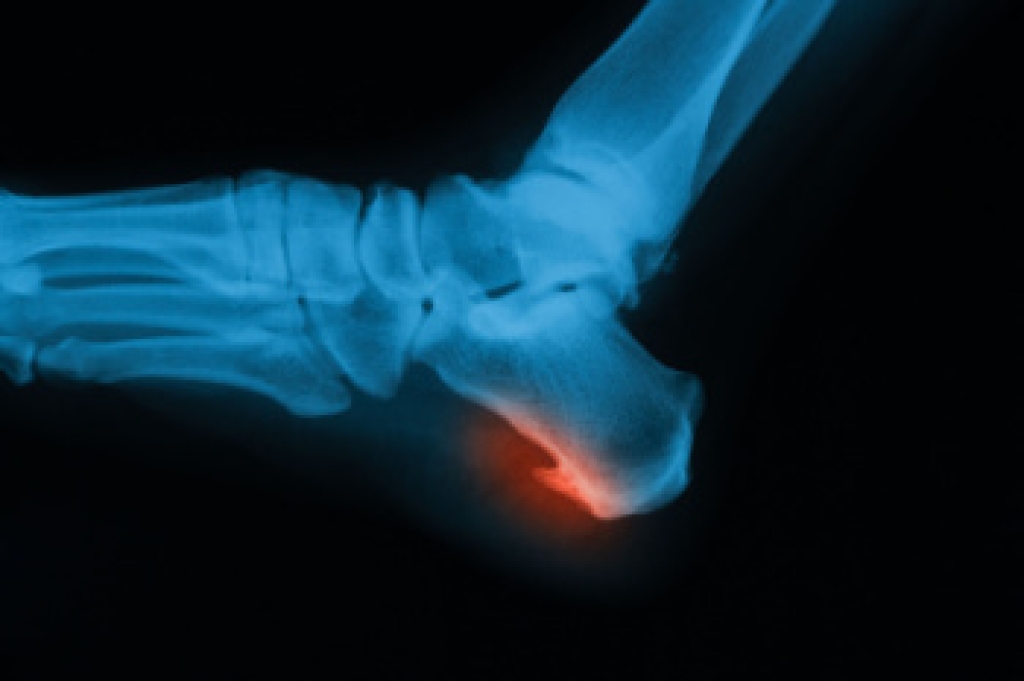

- Clubfoot, where tendons are shortened, bones are shaped differently, and the Achilles tendon is tight, causing the foot to point in and down. It is also possible for the soles of the feet to face each other.

- Vertical talus, where the talus bone forms in the wrong position causing other bones in the foot to line up improperly, the front of the foot to point up, and the bottom of the foot to stiffen, with no arch, and to curve out.